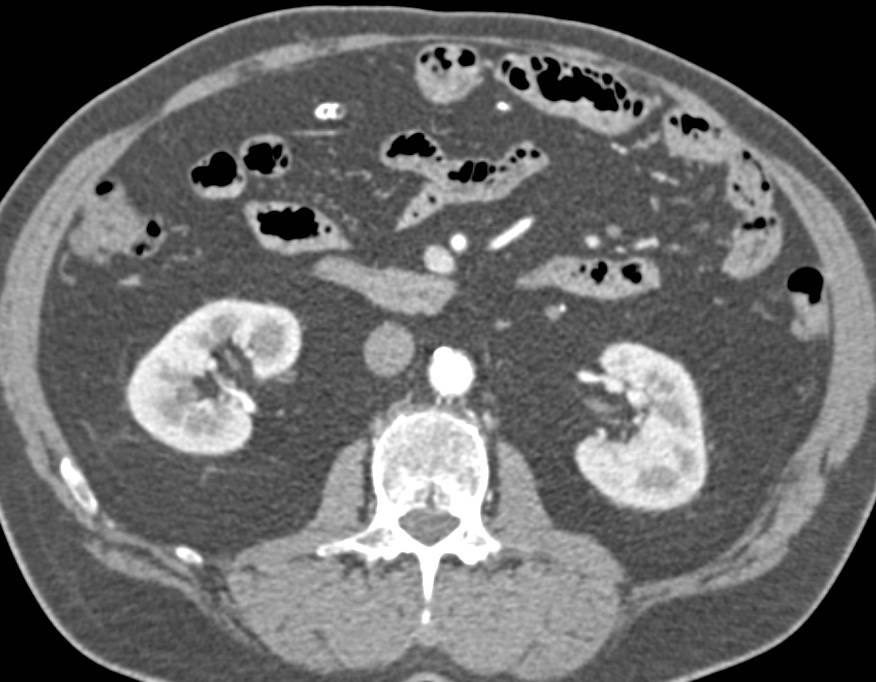

Celiac Artery Dissection